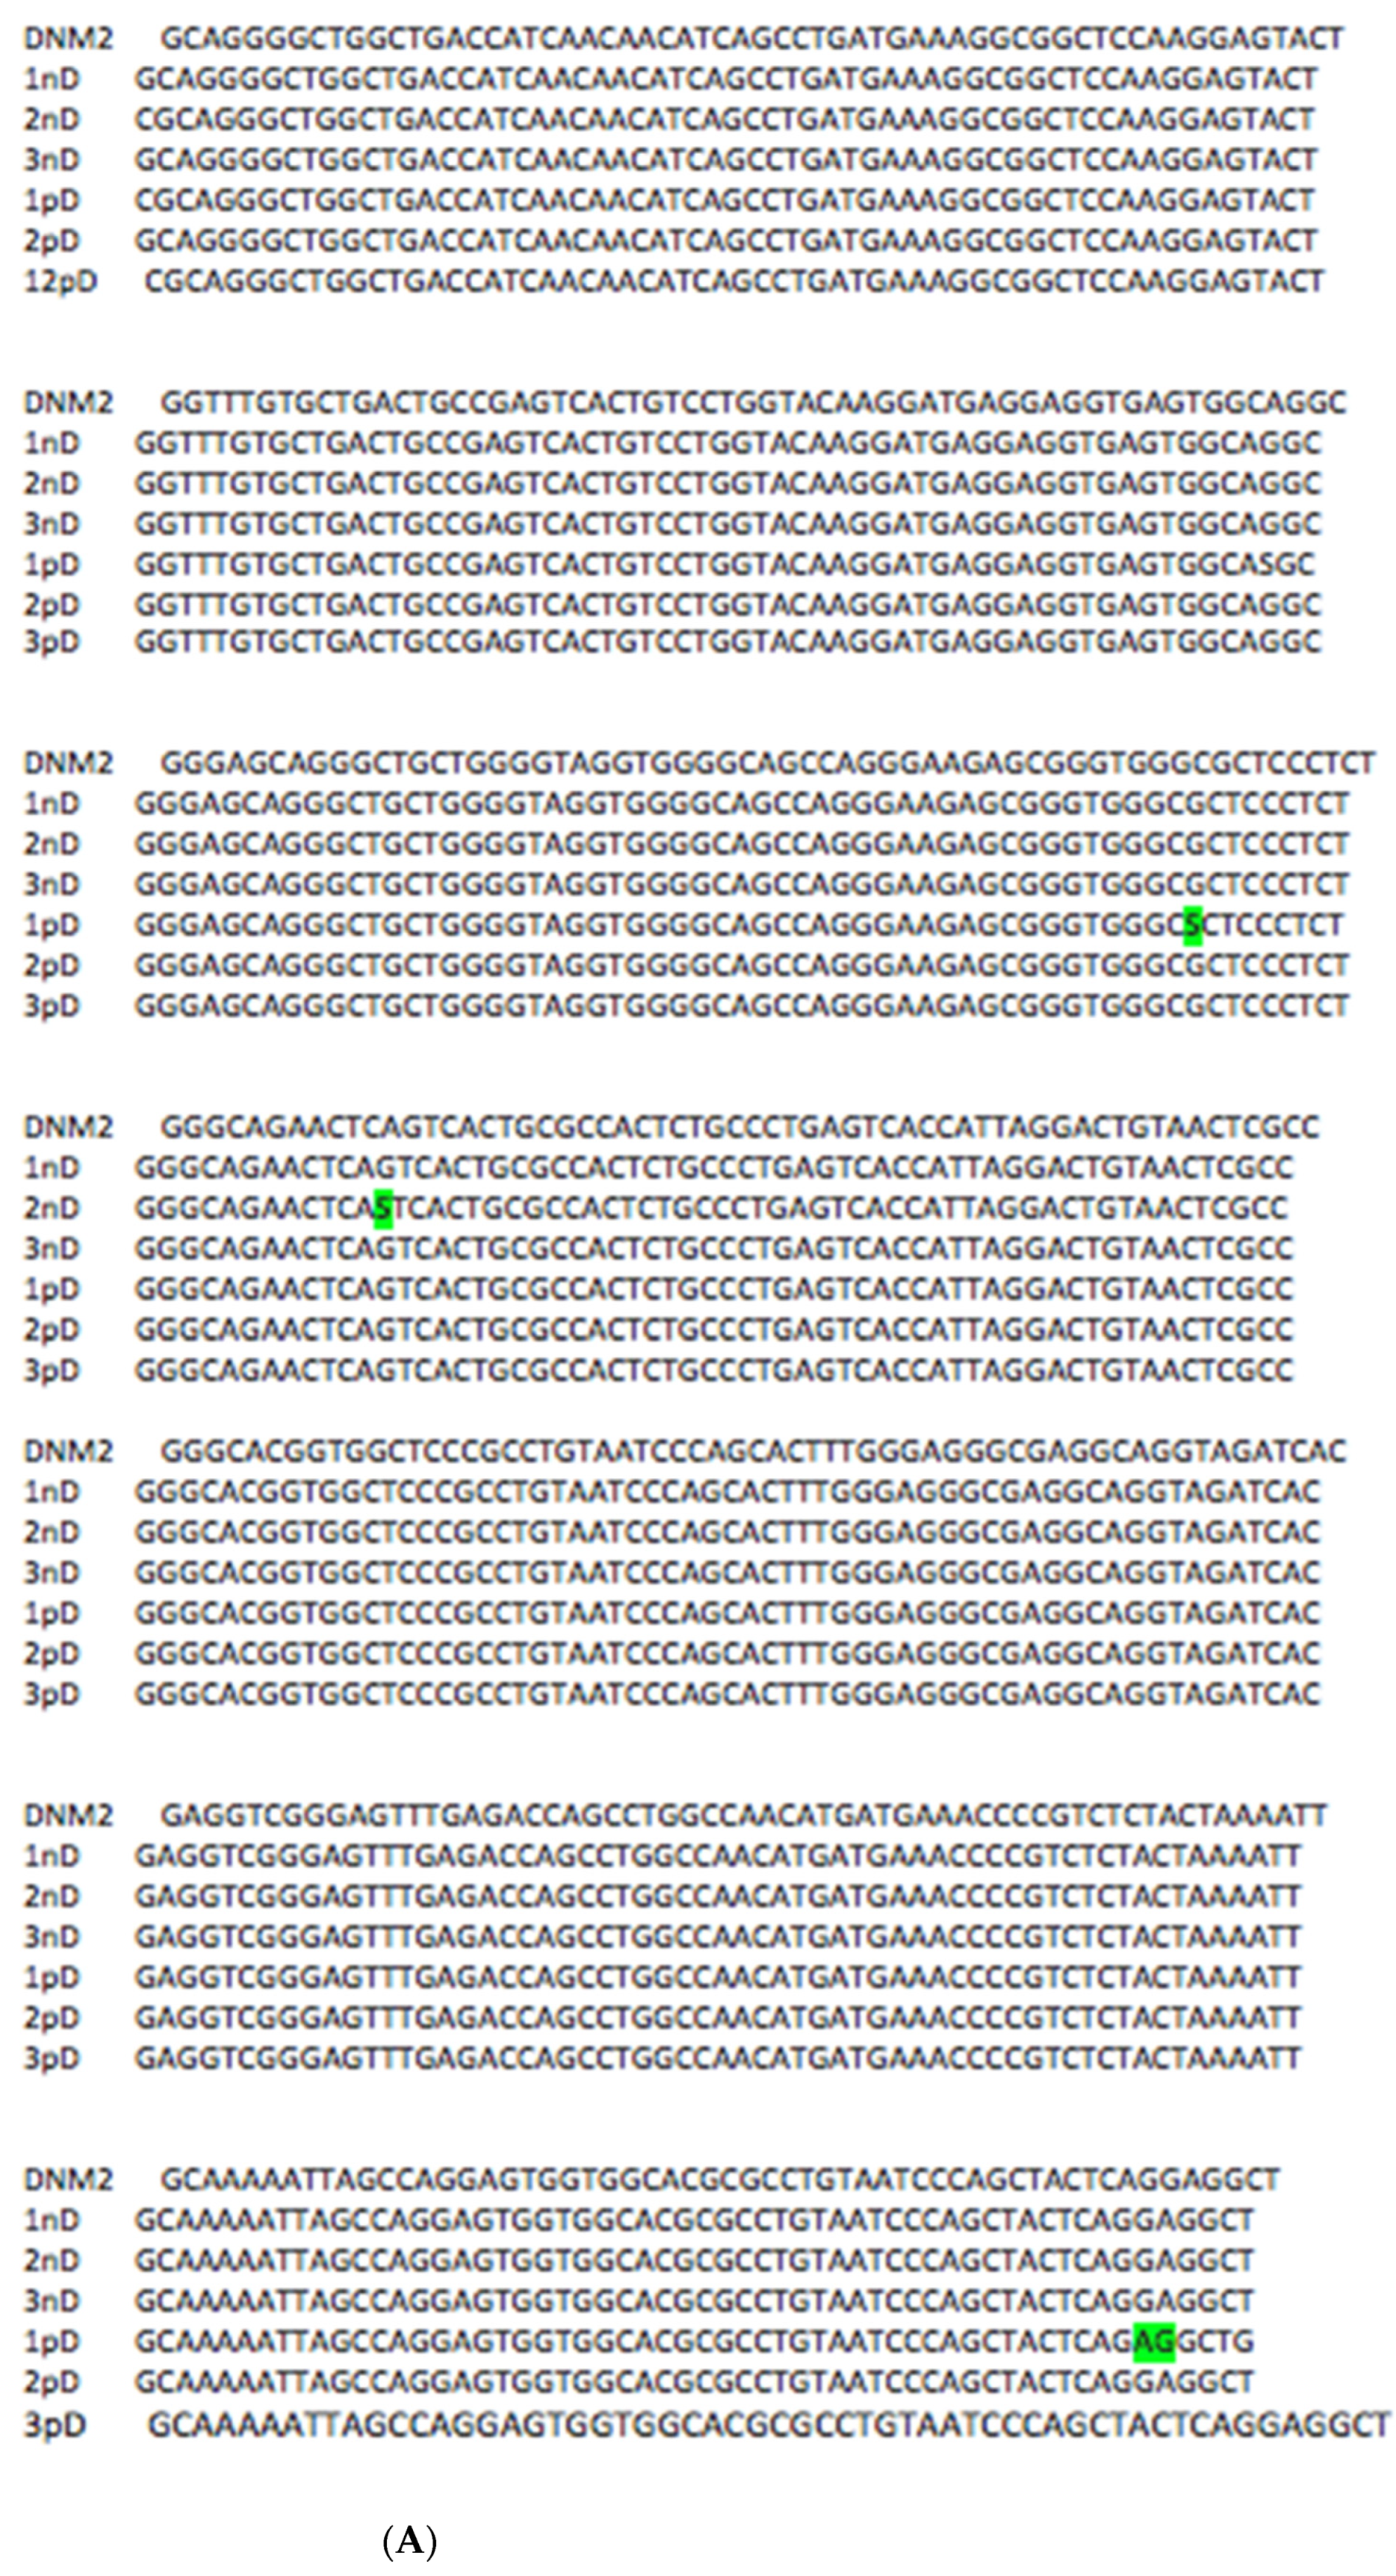

3. Results and Discussion